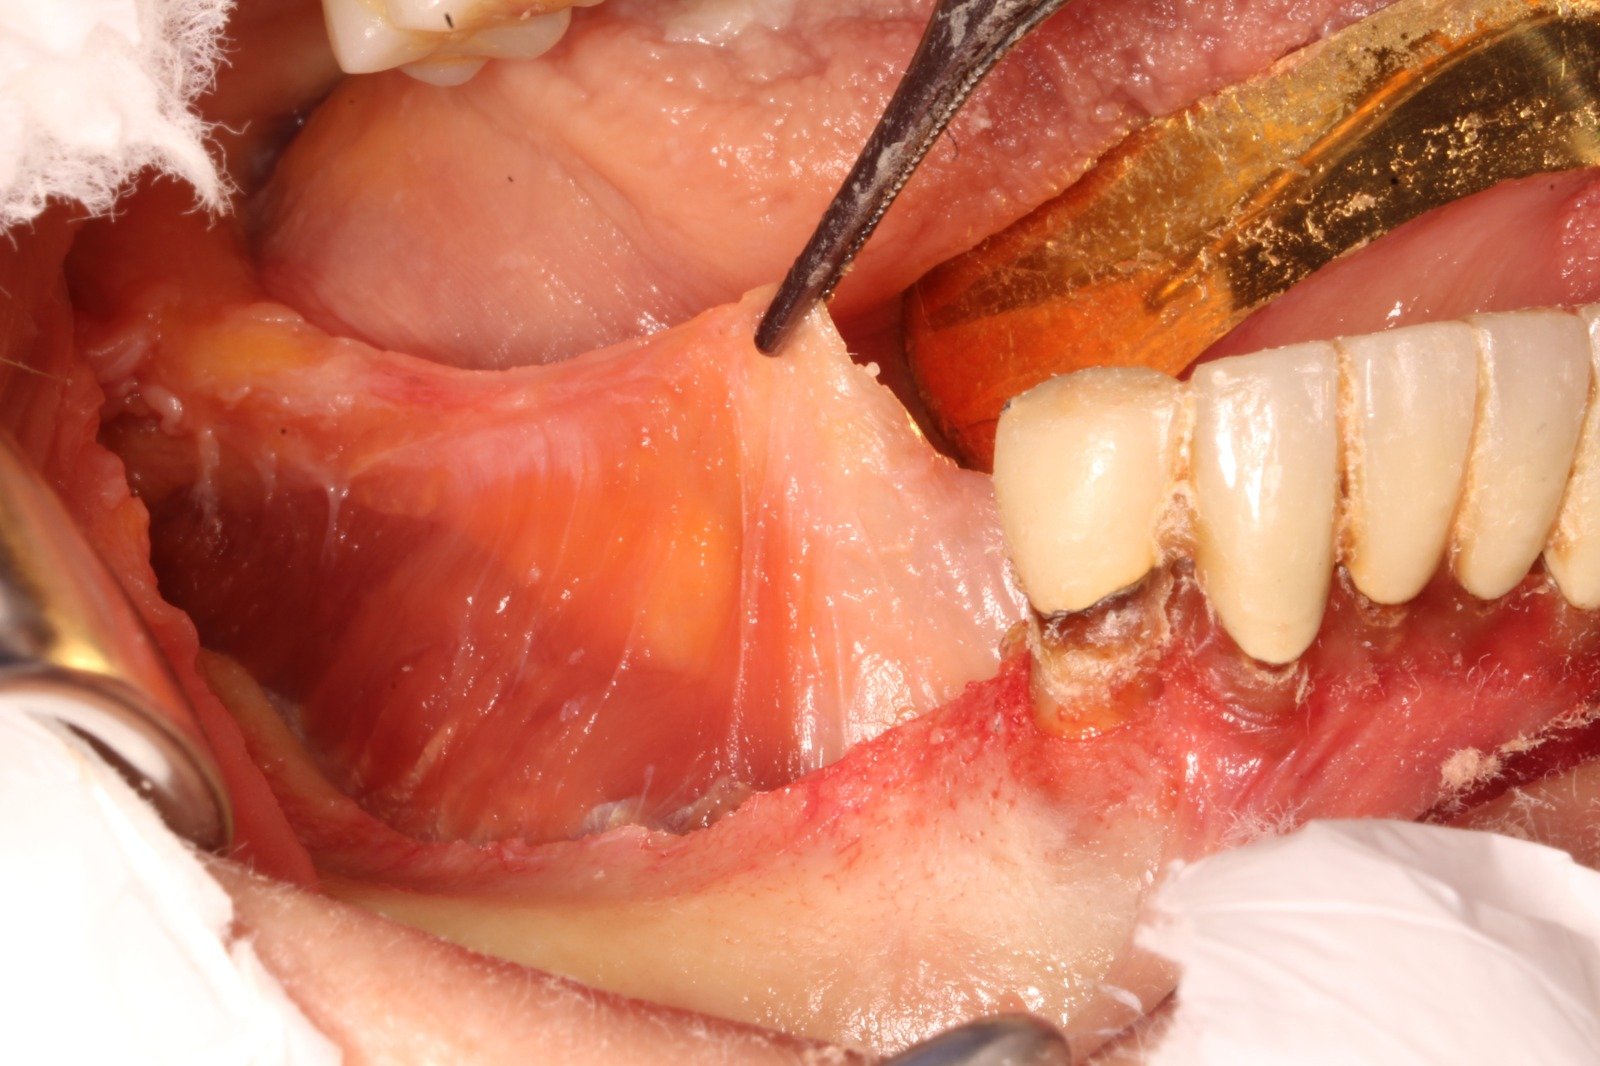

NO se entiende la Cirugía oral como la implantología hoy en día, sin regeneración. Tan importante es la elección del implante dental como la técnica regenerativa en cada caso.

- «Super membrana» de plasma con biomaterial

- Reposicionamiento del colgajo

- implante con regeneración horizontal simultanea